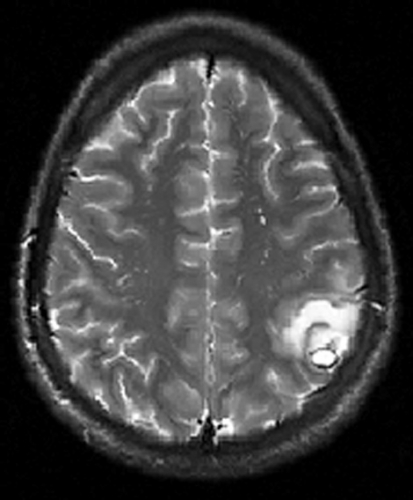

Datortomografi (DT) och magnetresonanstomografi (MRT) påvisade en solitär, drygt 1 cm stor rundad lesion i övergången mellan vit substans och kortex parietalt i vänster hjärnhalva. Förändringen var omgiven av en kontrastuppladdande kapsel och av ett ödem, som sträckte sig över hela den främre delen av vänster hemisfär (Figur 1 och Figur 2).

Differentialdiagnosen ur neuroradiologisk synvinkel omfattade bakteriell hjärnabscess och parasitinfektion, främst neurocysticerkos, men neoplasi (hjärntumör eller tumörmetastas) kunde inte med säkerhet uteslutas. Bilderna förmedlades via patientens familj till flera neurokirurger i patientens hemland, som samstämmigt ansåg att neurocysticerkos var mest sannolikt. I cerebrospinalvätska var antalet av polynukleära leukocyter diskret förhöjt (2,5 106/l). Western blot-analys av serum och cerebrospinalvätska påvisade inga antikroppar mot Taenia solium. Serologi för Toxoplasma gondii var negativ. I fecesdirektmikroskopi och i tejpprov fann man inga maskägg. Normalt ögonfynd konstaterades vid ögonläkarundersökning. Ett elektroencefalogram visade diffus förlångsamning med vänstersidig övervikt.

En kontroll-MRT-undersökning 18 dagar efter den första undersökningen (23 dagar efter anfallet) visade betydande regress av det perifokala ödemet och några millimeters minskning av själva lesionen. Kortikosteroidbehandlingen trappades ner och avslutades efter sammanlagt 21 dagar. Behandlingen med metronidazol och cefotaxim planerades att pågå i 6–8 veckor, enligt sedvanliga rutiner vid hjärnabscess som inte åtgärdas kirurgiskt. 30 dagar efter inkomsten fick patienten dock 39 graders feber och hade utvecklat en leukopeni (leukocytpartikelkoncentration 2,1 109 celler/l). Detta föranledde antibiotikabyte från cefalosporin till trimetoprim–sulfametoxazol.

En förnyad MRT-undersökning fem veckor efter det initiala anfallet visade åter en storleksökning av den intracerebrala förändringen och det perifokala ödemet.

Nästa steg är en DT- eller hellre en MRT-undersökning av hjärnan. Fynden i DT kan vara relativt ospecifika medan MRT ger bättre information om cystans innehåll. Vid neurocysticerkos ser man en eller flera cystor med kontrastladdande rand. Ibland kan parasitens skolex identifieras som en millimeterstor punkt, vilket gäller som ett säkert diagnostiskt tecken [6]. Äldre cystor förkalkas. Om den radiologiska undersökningen visar en patologi förenlig med neurocysticerkos analyseras serum eller cerebrospinalvätska med antikroppstest (immunblot-teknik enligt Tsang [7]). I Sverige utförs testet inte rutinmässigt, men prov kan lämnas till Smittskyddsinstitutet, som vidarebefordrar det till Schweiz. Testets specificitet anges till 100 procent, medan sensitiviteten varierar: upp till 95 procent vid multipla, icke-förkalkade intracerebrala lesioner och enbart ca 50–80 procent vid solitära cystor. Testet kan inte skilja mellan aktuell och genomgången infektion. Eosinofili i cerebrospinalvätska (men inte i blod) kan tyda på neurocysticerkos; differentialräkning av celler i cerebrospinalvätska kan genomföras manuellt i ett färskt likvorprov.